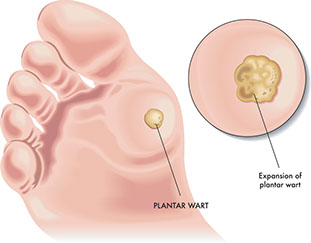

Planter Wart

Signs & Symptoms

Painful growth on the ball or heel of the foot. Black pinholes or spots in the center.

Self-Care / Prevention

* Try salicylic acid plasters or other over-the- counter products, such as Wart-Off. Follow package directions.

* Use cushions in shoes.

* Wash your hands after touching warts to avoid re-infection.

* Wear sandals in the shower or public areas, such as pools.

* Do not pick at plantar warts.